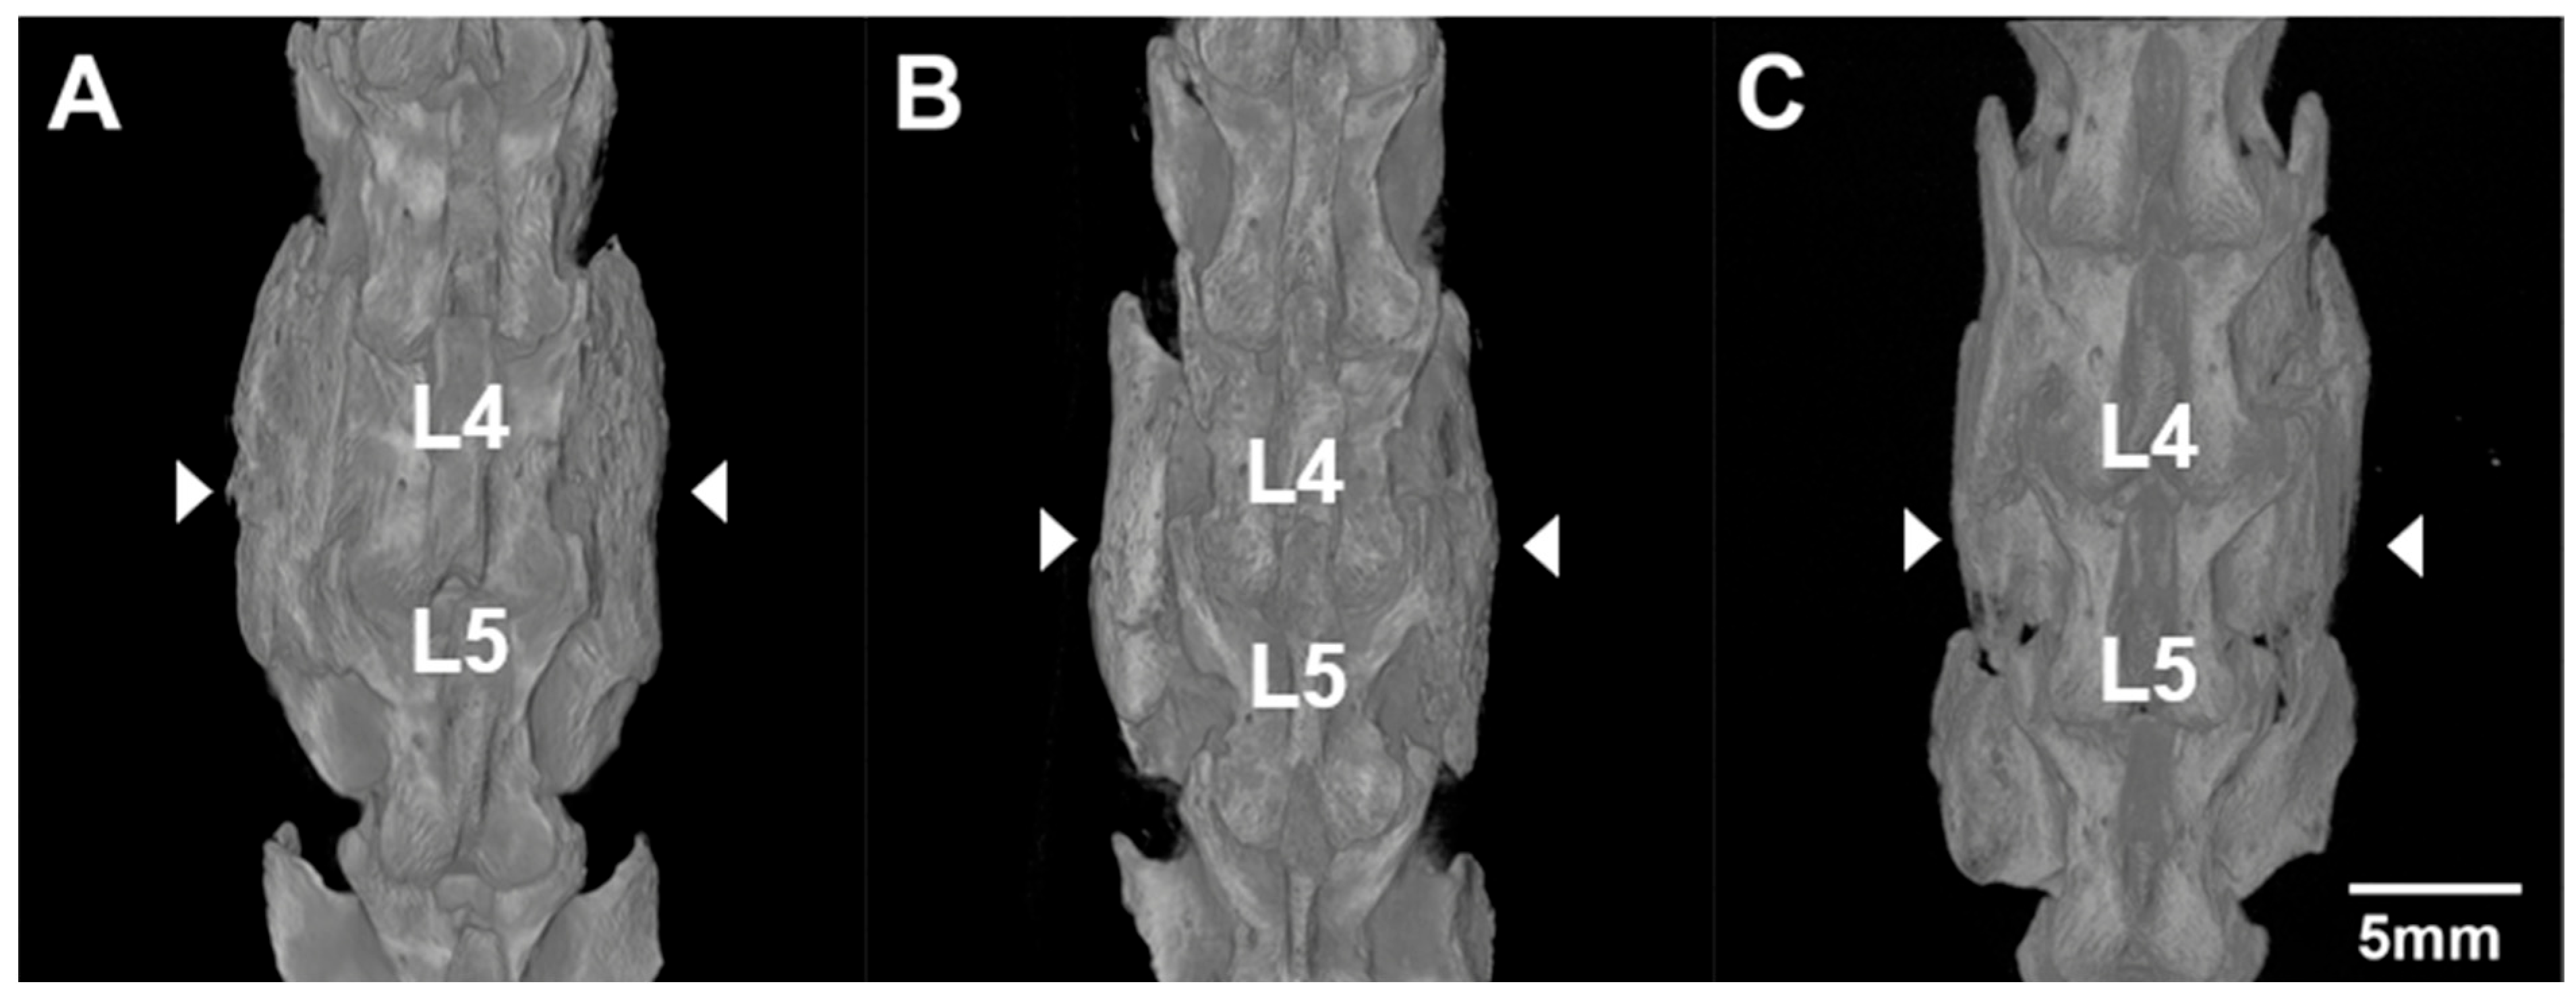

3.3. MicroCT and Assessment of Fusion